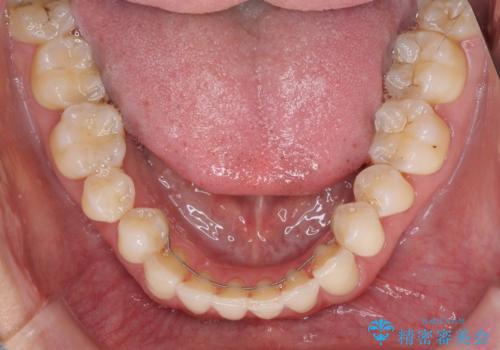

補綴治療に先立ち、下顎前歯の部分矯正を行い、前歯の咬み合わせの安定性向上を図りました。

当初は上顎の補綴治療のみを希望されていましたが、仮歯装着期間に上下の前歯の接触が気になったため、部分矯正を行うこととしました。

審美面と合わせて機能面も改善され、患者様には大変満足していただきました。